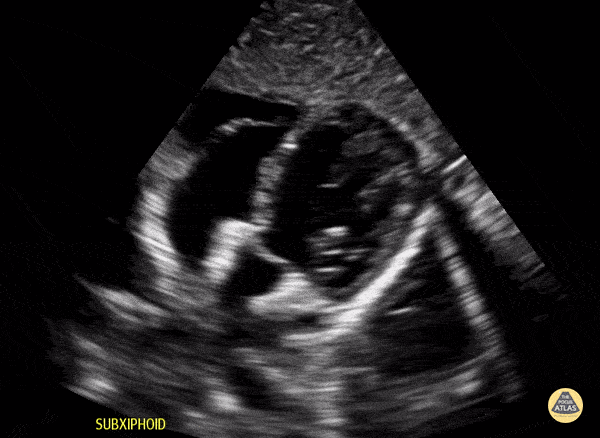

Normal subcostal view in a 4-year-old preschooler. Contributor: Jaron Smith, MD, Phoenix Children's Hospital